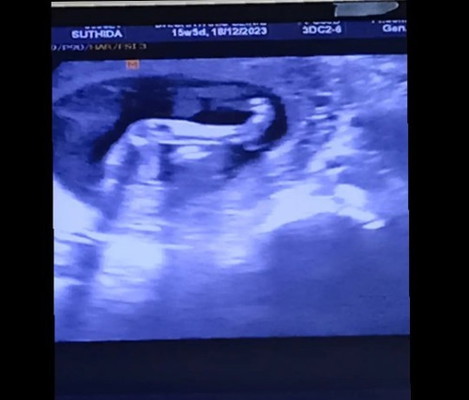

เมื่อวานไปพบคุณหมอตามนัด อายุครรภ์ 15+5week หมอซาวน์หน้าท้อง บอกว่าไม่พบถุงอัณฑะ อยากทราบว่า ตอนนี้ชัวร์รึยังค่ะว่าได้ลูกสาว ใจแม่อยากได้ลูกชาย (แต่คุณหมอแจ้งว่ายังไม่ชัวร์นะคะ เพราะน้องนอนชันขาแต่คุณหมอบอกว่าน่าจะผู้หญิง ต้องดูอีกครั้งถัดไป) แม่ ๆ คนไหนมีประสบการณ์ ซาวน์แล้วไม่เจอถุงอัณฑะแบบบ้านนี้บ้างคะ แล้วได้ลูกชาย ตอนนี้ยังลุ้นมาก อยากได้ลูกชาย เล่าประสบการณ์ให้ฟังกันได้นะคะ เผื่อแม่จะมีลุ้น ปล.แม่ไม่มีอาการแพ้ใด ๆเลยคะ ใช้ชีวิตแบบปกติมาก ไม่ชอบกินของหวาน หน้าไม่มีสิวเลย ใสมากก